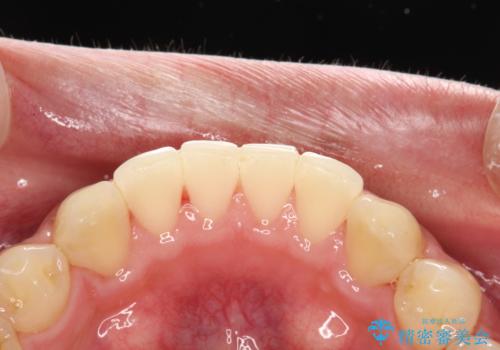

歯科衛生士によるクリーニング PMTC

- 半年ぶりの来院で、全体的なチェックとクリーニング希望でした。PMTC(自費クリーニング)60分コースを行いました。

PMTCとは、プロフェッショナル(歯科衛生士)メカニカル(機械的)トゥース(歯)クリーニング(清掃)の略です。歯科医院にて、いろいろな機械・材料を使用し汚れを落とします。

磨き残しや、細菌は歯の表面がザラザラしている部分につきやすいです。そのためPMTCを定期的に繰り返すことで、歯の表面がツルツルの状態である期間が長くなるため、虫歯や歯周病予防につながります。